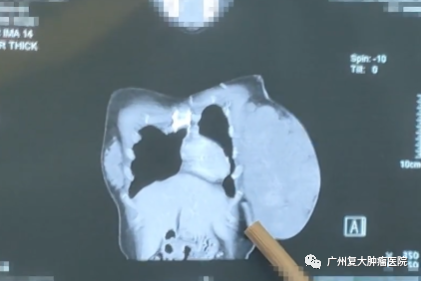

入院完善相關(guān)檢查后發(fā)現(xiàn),婷婷的左乳區(qū)域皮膚局部橘皮樣變,可捫及25×20cm大小腫物,穿刺活檢結(jié)果顯示為:乳腺腺病伴纖維腺瘤形成,未見癌。

結(jié)合檢查結(jié)果,我院專家開展復(fù)雜病例討論,一致認(rèn)為婷婷乳腺腫物巨大,但皮膚及胸大肌未見明顯粘連侵犯,不排除良性腫瘤可能,有手術(shù)指征,建議術(shù)中冰凍明確診斷,若為良性,則進(jìn)行左乳腫物切除術(shù),若為惡性,則實(shí)行改良根治術(shù)。

所幸術(shù)中快速病理回報(bào)未見惡性。一切依計(jì)劃進(jìn)行,醫(yī)生仔細(xì)分離腫瘤以及周圍正常組織,游離皮瓣,順利將腫瘤組織切除,解除了患者的巨大腫瘤負(fù)荷。切除的巨大腫瘤標(biāo)本足有6斤重,大小約23×16×12cm,婷婷開玩笑說,這腫瘤可比我小孩出生還要重。